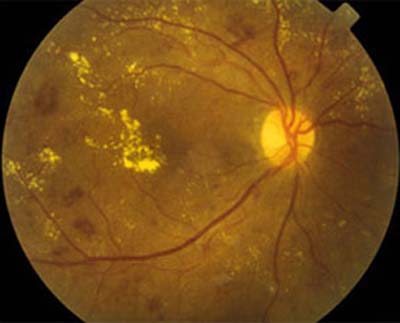

Retinopatía Diabética

Retinopatía Diabética No Proliferativa (RDNP): En un individuo sano, los vasos sanguíneos de la retina solo permiten la salida de nutrientes y oxígeno hacia la retina (no de líquido o plasma). En las personas con retinopatía diabética el contenido de los vasos (sangre y plasma) puede salir de ellos de manera anormal debido a la lesión de sus paredes por los altos niveles de glucosa. Esta acumulación de líquido en la retina dificulta su funcionamiento.

Retinopatía Diabética Proliferativa (RDP): Debido a la continua lesión que sufren los vasos sanguíneos por los elevados niveles de glucosa, muchos de ellos terminan por cerrarse completamente impidiendo la llegada de sangre y nutrientes a la zona de la retina que antes irrigaban. Estas zonas de la retina intentan obtener oxígeno y nutrientes produciendo nuevos vasos sanguíneos. Desafortunadamente estos nuevos vasos (neovasos) no tienen una función normal y crecen no sólo dentro de la retina, sino hacia el vítreo (hacia el centro del ojo, donde no debe haber vasos sanguíneos). Son estos neovasos los que pueden sangrar y producir hemorragias vítreas o pueden halar la retina para desprenderla.

La Retinopatía Diabética es la primera causa de ceguera en U.S.A. y una de las más importantes en nuestro medio. El 25% de diabéticos tienen alguna forma de retinopatía y sólo un 10% no la presenta durante su vida.

Al tener niveles altos de azúcar (glucosa) en la sangre, como los generados por la Diabetes, se produce daño del endotelio vascular (parte importante de la pared de los vasos sanguíneos) que afecta la totalidad del sistema circulatorio del cuerpo, incluyendo los vasos sanguíneos de la retina en el ojo.

¿Cómo produce ceguera con la Retinopatía Diabética?

La retina es la parte del ojo más importante para la visión. Es allí donde la luz se convierte en impulsos eléctricos para que las imágenes sean interpretadas por el cerebro. La diabetes puede llevar a un mal funcionamiento de la retina de tres formas principales:

- Edema Macular: Acumulación anormal de líquido entre las finas capas de la retina (en la mácula, el sitio de mayor sensibilidad de la retina). El engrosamiento de la mácula impide su función adecuada. El líquido proviene de los vasos sanguíneos cuyas paredes tienen una función alterada a causa de la Diabetes.

- Hemorragia Vítrea: En fases más avanzadas de la retinopatía, se forman dentro del ojo nuevos vasos sanguíneos (neovasos) que se rompen con gran facilidad. Al romperse liberan sangre dentro del ojo, lo que impide el paso de la luz hacia la retina.

- Desprendimiento de Retina: También en fases avanzadas de la enfermedad, se puede desprender la retina, principalmente por tracción ejercida por el vítreo y los neovasos. Al desprenderse la retina, pierde su fuente de nutrientes y por lo tanto su función.